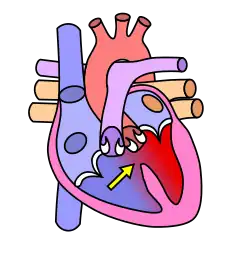

Dans le cœur normal, la cloison qui sépare les ventricules droit et gauche, dénommée « septum interventriculaire », est totalement hermétique. Une CIV correspond à la présence d'un orifice plus ou moins large dans cette cloison, permettant le passage direct du sang d'un ventricule à l'autre. Les conséquences de cette malformation dépendent essentiellement de la taille de la communication. Dans la plupart des cas, l'orifice est petit : ces CIV sans conséquence réellement gênante sont appelées « maladie de Roger ». L'évolution d'une CIV dépend de sa localisation sur le septum, certaines étant susceptibles de se fermer spontanément dans les mois ou années suivant la naissance.

Shunt droit-gauche

Le sang non oxygéné passe dans le ventricule gauche, causant une cyanose[1]

- C'est le cas des CIV qui siègent dans le septum d'admission (partie 1 en rouge sur le schéma), fréquemment associée à une Trisomie 21, et de celles qui siègent dans le septum sous-aortique (partie 4 en bleu sur le schéma), parfois associées à une anomalie du chromosome 22 (Microdélétion 22q11) ;

- les CIV siégeant dans le septum membraneux (partie 3 en jaune sur le schéma) et encore plus les CIV musculaires situées dans la partie 2 (en vert sur le schéma) sont fréquemment capables de « se guérir toutes seules » (à condition que l'état de l'enfant permette d'attendre).

- les CIV situées dans les parties 1 (septum d'admission) et 4 (septum sous-aortique) ne se ferment jamais spontanément et devront donc, sauf exception, être opérées tôt ou tard.

Schéma sur les localisations des communications interventriculaires (légende) :

- CIV membraneuse et péri-membraneuse (1-2-3)

- CIV d'admission ou postérieure (4)

- CIV musculaire ou trabéculée (5-6)

- CIV sous-aortique (7)

- CIV infundibulaire (8).